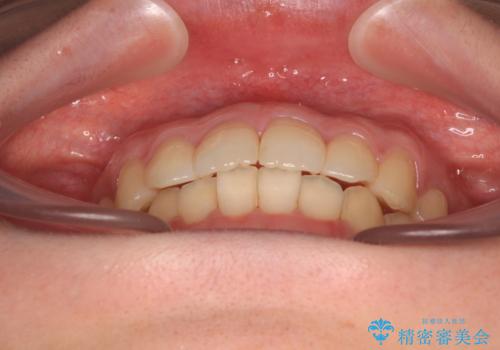

デコボコ歯列をきれいに インビザラインによる矯正治療

- 上下歯列全体のデコボコを気にして来院された患者様です。

主に下顎歯列全体の後方移動とIPR(歯と歯の間を削る)によってデコボコが解消するように設計し、インビザラインにより治療を行うこととしました。

1年半程度で終了するのではないかと予想しましたが、途中1年以上の来院がなく、トータルで3年の時間がかかってしまいました。

前歯のデコボコはより改善することが望ましい状態でしたが、患者様の希望により終了することとなりました。